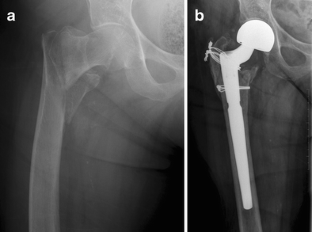

Fig. 1

Fig. 2